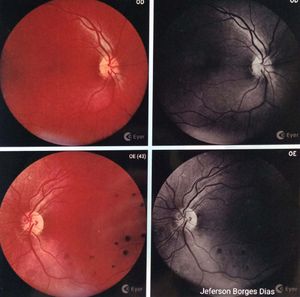

Em 2015, Jerfeson foi diagnosticado com trombose nas vistas, que resultou na perda de visão do lado esquerdo e colocou em risco a visão do olho direito. Desde então, tem sido uma jornada desafiadora para nós. Conseguimos realizar duas cirurgias oftalmológicas, uma a laser e outra com injeção intraocular, no setor particular, mas, infelizmente, devido aos custos elevados, não podemos continuar com os tratamentos recomendados a cada seis meses. (No início do tratamento).

Criamos esta vaquinha online com o objetivo de arrecadar fundos para cobrir os custos das aplicações oftalmológicas de Jerfeson. Cada contribuição, por menor que seja, faz a diferença e nos aproxima do objetivo de salvar a visão dele. Pela situação do Jerfeson hoje com ajuda de um amigo conseguimos realizar os exames e pela gravidade da situação as aplicações teram que ser feitas de mês a mês para vermos uma esperança de possível melhora nos edemas após romper a retina. Não temos esse recurso. Por ele não estar trabalhando pelas dores. E não poder pegar sole nem se esforçar.